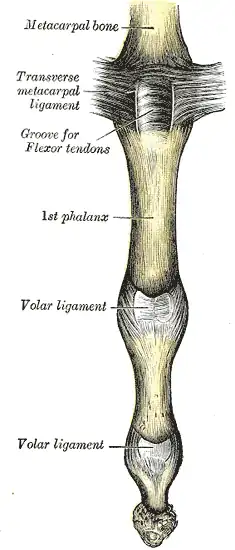

Metacarpophalangeal articulation and articulations of digit. Volar aspect.

Metacarpophalangeal articulation and articulations of digit. Volar aspect. Metacarpophalangeal articulation and articulations of digit. Ulnar aspect.